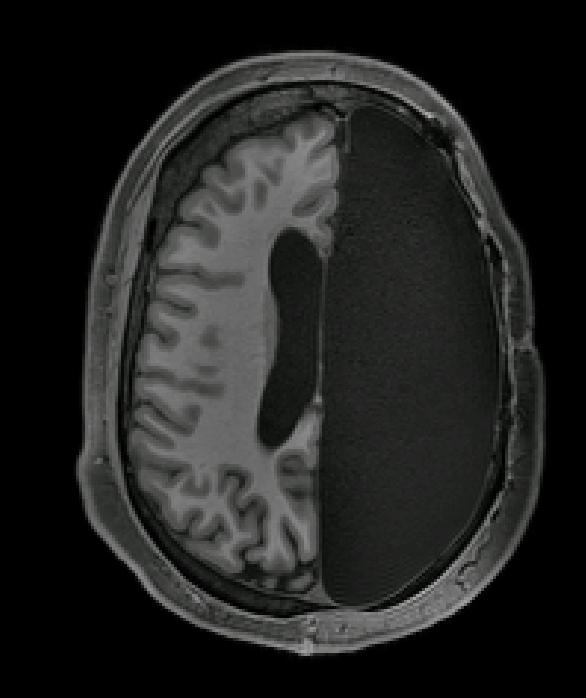

It almost seems impossible to think of a life like that but there are active cases where individuals are leading their life with just half part of the brain by birth or surgical removal of diseased part of brain, called hemispherectomy as measure to treat seizures and other neurological disorders which does not respond to medicines.

Well, that’s perhaps because the body of person with such condition adapt changes by making certain neurological activities from the disconnected or missing half of their brain shifted to other half. This is a property of brain is known as neuroplasticity, that can be defined as the ability of brain to adapt the changes as a result of experience through growth and reorganization of the tissue, which makes surgeries like hemispherectomy a successful method to treat patients with epilepsy or any other neurological issues. In epilepsy, the brain wiring changes abnormally which results in mild sensation, changes in behaviour and often loss of awareness. Through hemispherectomy, the part or half of brain in patients are either removed or made disconnected from the other parts of brain physically, and it was found out that the majority of them made a recovery against it. “The people with hemispherectomy that we studied were remarkably high functioning,” said Dr. Dorit Kleiman, a post-doctoral fellow at California Institute of Technology. Moreover, they had strong brain connections between numerous functional networks. The only condition being, these surgeries to be performed at an early age, as the neuroplasticity is heightened during childhood as compared to adults (Fatima Yousif Ismail, et al., 2006) enabling the brain to reconstruct and body to adapt new changes accordingly.